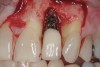

Why implant cement should cause an issue is unclear, as is to what extent the cement plays a part in the process. It is possible that the cement is simply passive and acts as a physical bacterial trap—similar to an overhang on a restoration or calculus effects on the natural dentition (Figure 3). It is also possible that the cement plays a more active role because the destruction of both hard and soft peri-implant tissues is frequently aggressive and extensive (Figure 4 and Figure 5). The disease may be different between patients—and even within the same patient; it may be due to either one major primary factor or a combination of factors.

Figure 3

Figure 4

Figure 5